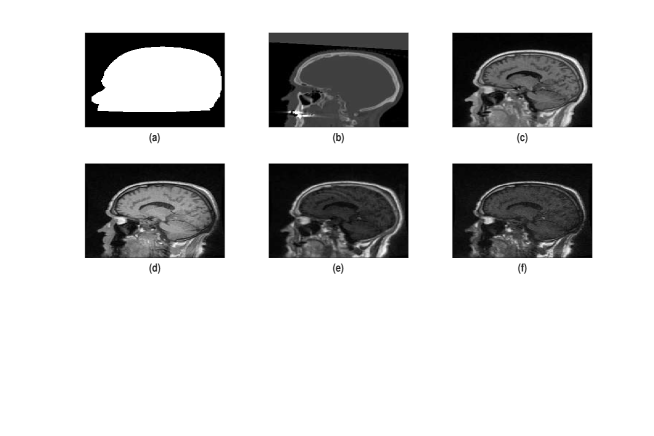

CT and MR images were obtained from head of five patients. Four MR images were acquired from each patient using two dual echo ultrashort echo-time sequences with flip angles of 10 degrees and 30 degrees. The ultrashort echo-time sequences sampled a first echo (free induction decay) and a second echo (gradient echo) from the same excitation with an echo time of 0.07 and 3.76 milliseconds. MR image of a patient was reconstructed to 192×192×192192192192192\times 192\times 192 matrix. An entry in the matrix represents a signal intensity corresponding to a three dimensional tissue (voxel) with size 1.33 ×\times1.33 ×\times1.33 mm3. One CT image of a patient was acquired using gradient echo Lightspeed with 2.5mm slice thickness. The acquired CT image was reconstructed with an in-plane resolution of 0.78 ×\times 0.78 mm2. One binary mask (an image with voxel value 1 (or 0) representing the region of interest (or the surrounding air)) was also developed to demarcate the head of a patient from its surrounding air. The main use of the binary mask is to exclude the surrounding air from the acquired CT and MR images. For each patient, the binary mask, the CT image, and the four MR images were co-registered and resampled to the same resolution (voxel-to-voxel correspondence and set to the same voxel dimension) using linear interpolation. For further technical details, we refer to Johansson et al. [10]. Voxel values of the CT image, the binary mask, and the four MR images were organised into six columns to obtain data for a patient. The organised data of each patient were column stacked and the surrounding air removed to obtain data for model fitting. Figure 1 shows a slice data for a given patient.

Refer to caption

Figure 1: Binary mask ((a)), CT image ((b)) and MR images ((c)-(f))